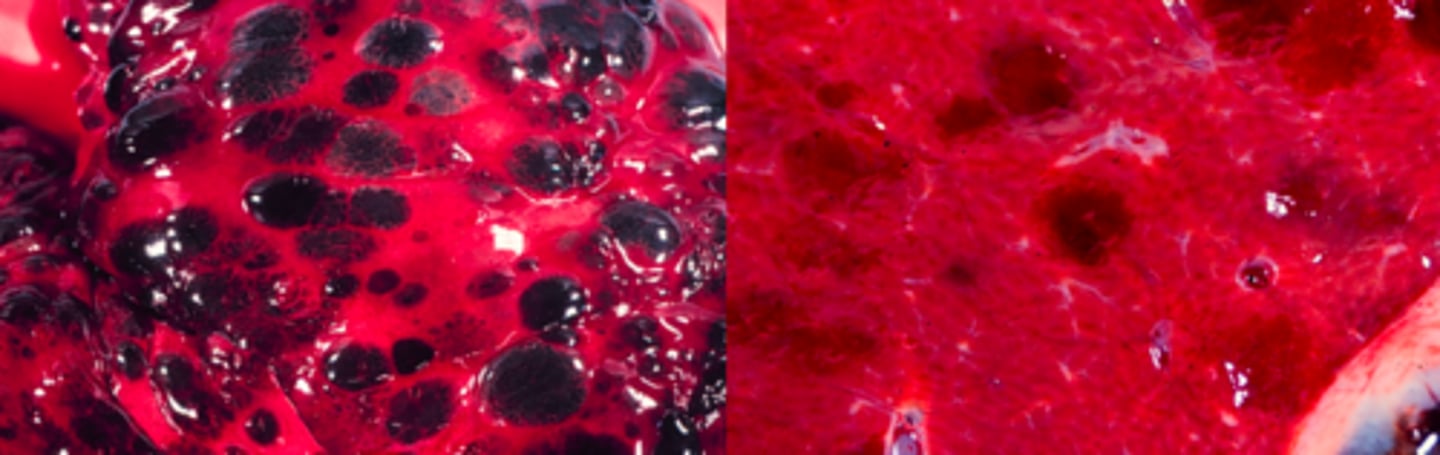

Fokal Kapillærektasi (teleangiektasi)

årsagen er ukendt

Er udvidelse af sinusoiderne

Lever, hvad er den patoanatomiske diagnose?